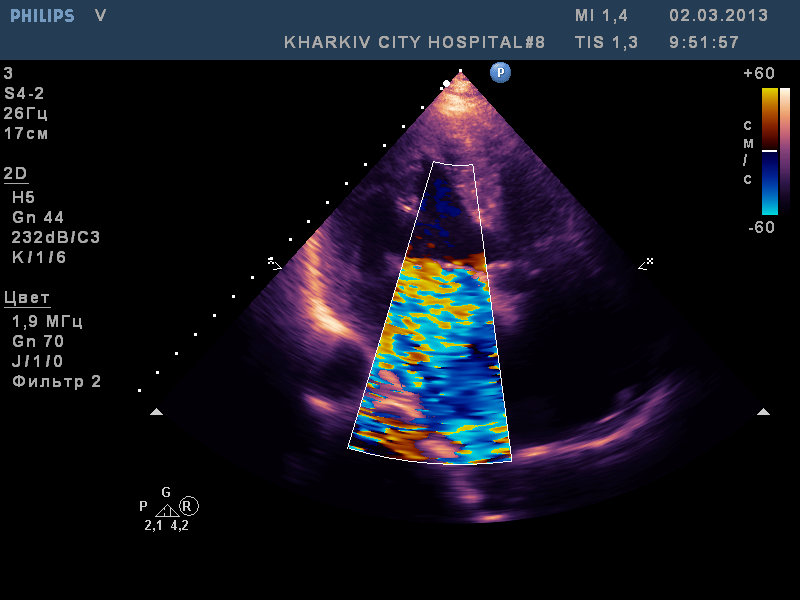

Пациентка (доктор, на пенсии). Направлена с терапии для ЭХО-КС. В анамнезе пролапс МК, субфебрильная температура.

При осмотре пролабирование задней створки до 9.2мм, выраженная недостаточность, дилатация предсердия до 5.0см и подвижная структура на задней створке. Гидроперикард (незначительное количество жидкости). Выпот в плевральные полости.

Коллективно посмотрели. Похоже что есть свежие вегетации на свободных краях створок МК на фоне ПМК.

Как представляется у пациентки имеется ПМК с миксоматозной дегенерацией и вегетации на предсердной поверхности клапана. Все это привело к недостаточности митрального клапана тяжелой степени.

Вызывает сомнение отсутствие легочной гипертензии.